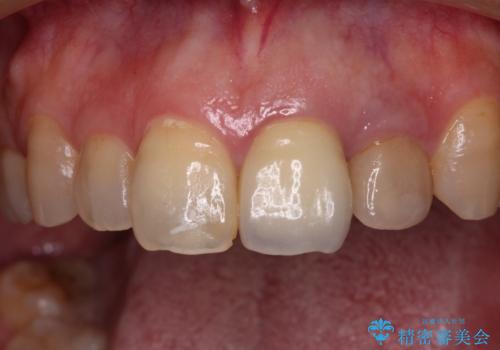

真ん中のオールセラミッククラウンを正面から見ると大変自然に仕上がっているのですが、側方から見ると白色が強く、さらには隣の歯は神経が除去されて変色していたため、コントラストでより色の違いが際立っていました。

前歯2本をオールセラミッククラウンにて補綴治療することとしました。